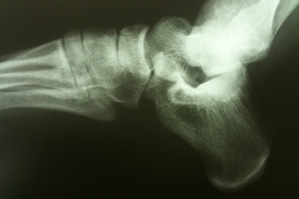

One in particular has to do with barefoot running. In case you haven’t heard, word on the street lately is that running shoeless provides a lower impact exercise option than your standard sneakered job. In a way, the logic makes sense. It’s supposed to be more “natural.” Sneakers allow us to strike the ground with the heels of our feet because they have synthetic padding. But without sneakers, the heel strike sends a spike of pressure shooting through our joints. Since we evolved with no Nike to speak of, we should be naturally inclined to strike at the balls of our feet instead of our heels.

So why then do so many people suffer from sports injuries soon after starting up a barefoot running regimen? The answer also makes sense: because they’re not used to it. If you’ve spent your whole life walking around in shoes, then suddenly running a mile without them could quickly wreak havoc on your body. That’s because your calves and Achilles tendons aren’t strong enough to absorb the new level of impact — the sneaks have been taking care of that this whole time.

Nolan said he sees injured barefoot runners who claim that they’ve completely changed thier gait from a “heel strike” to a “midfoot strike” but when they hook ’em up in the lab, the data tells a different story. Nolan says it can take as long as six months before a full transition has been made, and that even if we’re marathoners, we can’t expect to run as far and as long right away without shoes. “If you don’t do it thoughtfully, you’re setting yourself up for injury,” he said. “It’s too much of a good thing too fast.”